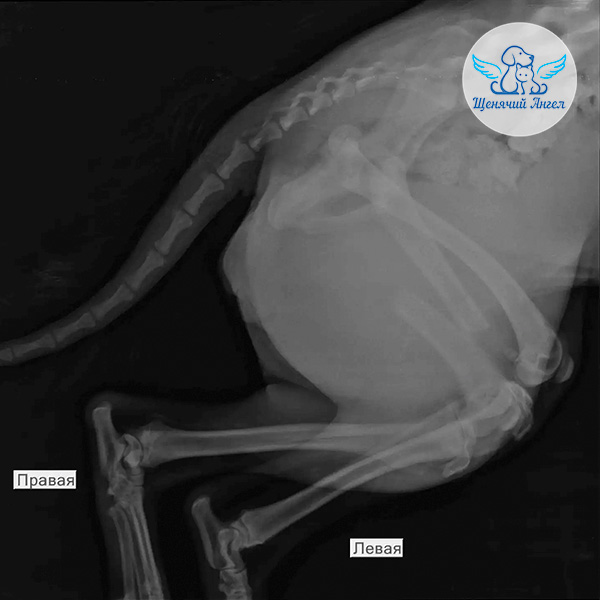

🙏🏻 Благодаря вашей помощи нам удалось забрать малышку и срочно доставить в местную ветеринарную клинику. Там Дуню обезболили и провели первичную диагностику. Рентген показал перелом левой задней лапы, также есть подозрение на перелом костей таза 🩻

Несколько дней Дуня находилась в стационаре – врачи стабилизировали её состояние и сняли острый болевой синдром. Как только транспортировка стала безопасной, мы перевезли Дуню в Москву, в клинику «Animal Vet», где сейчас она находится под круглосуточным наблюдением специалистов 🏥

По прибытии были взяты необходимые анализы на инфекционные заболевания 🦠. В ближайшие дни запланированы осмотр хирурга и повторный рентген – по их результатам будет определен план дальнейшего лечения и операции ❤️‍🩹